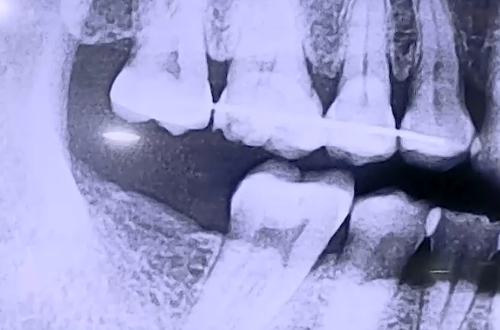

AFTER

임플란트가 굳기까지 3개월을 기다린 뒤 보철을 완성해드렸고,

윗니도 더 내려오지 않아 문제 없이 치료를 마무리할 수 있었습니다.